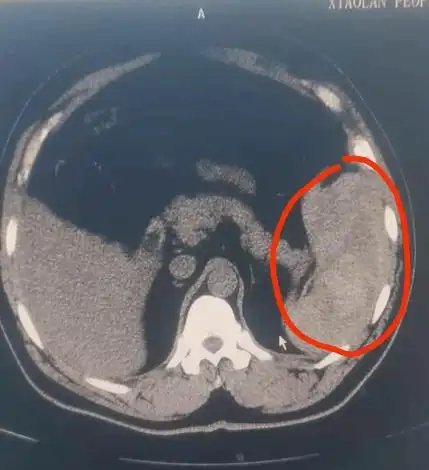

可卡因引起的无创性脾破裂

脾脏破裂,周围积血.

张阿姨腹部ct显示:脾脏破裂,腹腔积血.